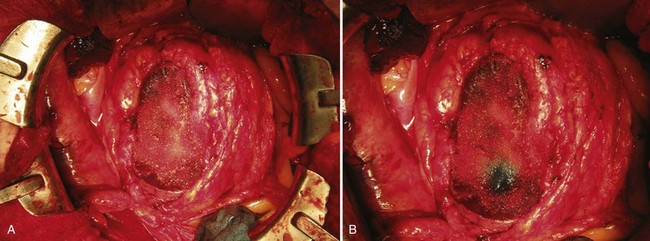

An anterior cavotomy is made using Potts forward and reverse scissors. The cavotomy should circumscribe the ostium of the renal vein and extend to the minor hepatic veins above the caudate lobe of the liver. The field will be nearly bloodless. For tumor extending into the right atrium the atrium is also opened (Fig. 54–115). The thrombus is extracted with the patient in Trendelenburg position and using positive-pressure respiration. If possible, the tumor thrombus is removed intact along with the kidney, although the thrombus may need to be removed in pieces if it is friable or adherent to the caval wall (Fig. 54–116). When necessary, a Fogarty catheter is passed from the atrium into the hepatic veins to retrieve portions of tumor thrombus. The authors ensure that tumor thrombus removal is complete by performing venacavoscopy with a flexible cystoscope. The cavotomy is closed with a double-armed 4-0 polypropylene running suture. The atriotomy is closed. Radical nephrectomy is carried out while rewarming to 37° C and coming off bypass. The patient is decannulated. Protamine is administered to reverse the heparin. Any leaking areas on the IVC are repaired with interrupted 4-0 polypropylene sutures. The abdomen is drained, and chest tubes are placed. Fresh frozen plasma, platelets, and desmopressin are used if needed to treat coagulopathy.

Figure 54–115 A and B, Tumor thrombus extension into right atrium removed using traditional median sternotomy approach and an atriotomy for retrieval of thrombus. IVC, inferior vena cava.